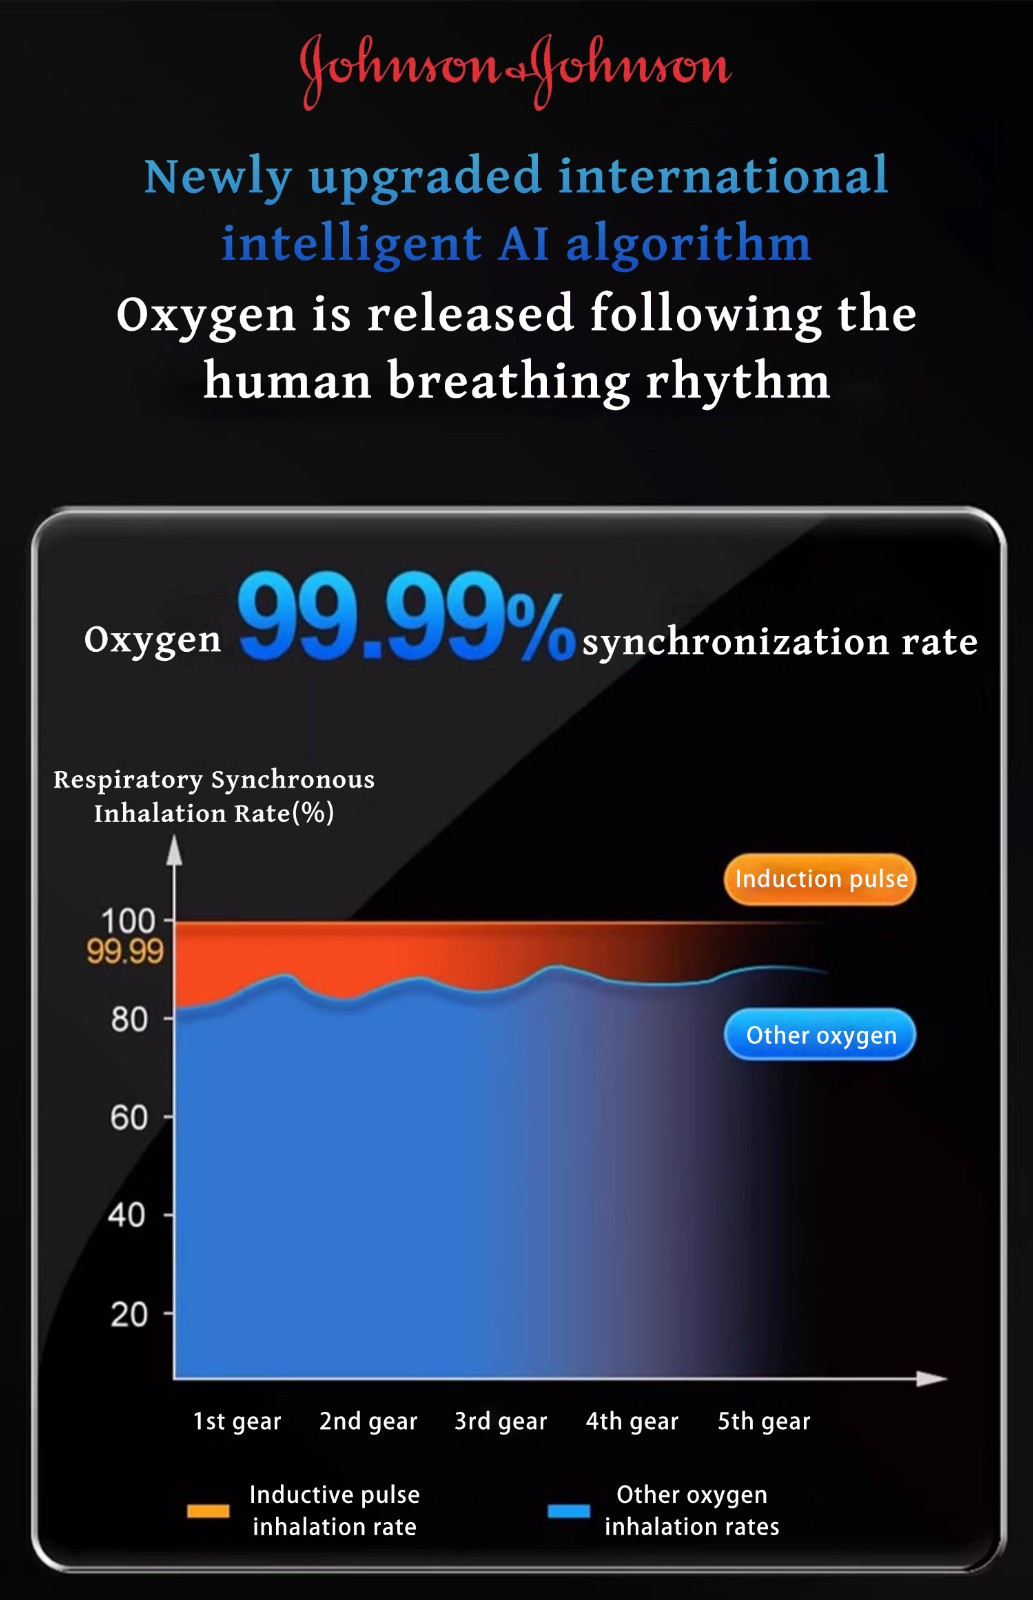

Ο συμπυκνωτής οξυγόνου που πουλάμε είναι ένα προϊόν που αναπτύξαμε μετά από 5 χρόνια έρευνας και ανάπτυξης. Μετά την κυκλοφορία του, έλαβε ομόφωνους επαίνους από αμέτρητους αναπνευστικούς ασθενείς και πουλήθηκε σε εκατοντάδες χώρες σε όλο τον κόσμο.